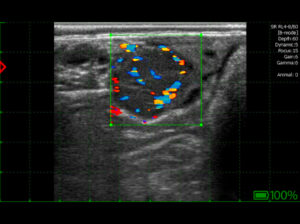

Bildqualität

Obwohl Untersuchungen bei Rindern nicht die gleiche Präzision wie in der Kleintierchirurgie erfordern, ist ein klares und kontrastreiches Bild unerlässlich. Es ermöglicht die Beurteilung der Ovarstrukturen, das Erkennen von Zysten, Follikeln und Gelbkörpern, die präzise Bestimmung des Trächtigkeitsalters, die Diagnose von Pathologien der Gebärmutter, wie Pyometra oder Flüssigkeitsansammlungen, sowie die Kontrolle nach Eingriffen, z. B. Punktion einer Zyste. Wichtige Faktoren sind Auflösung, Sondenfrequenz, Eindringtiefe und die Möglichkeit, Bildparameter in Echtzeit anzupassen.

Standard bei der Arbeit mit Rindern ist eine lineare rektale Sonde – lang und schmal, für rektale Untersuchungen geeignet. Sie sollte ergonomisch, widerstandsfähig gegen Beschädigungen und Flüssigkeiten sein. Eine Frequenz von 5–9 MHz bietet einen guten Kompromiss zwischen Auflösung und Eindringtiefe. Fortgeschrittene Geräte ermöglichen auch den Anschluss von konvexen Sonden für Oberflächenuntersuchungen oder Doppler-Sonden zur Beurteilung von Blutfluss.